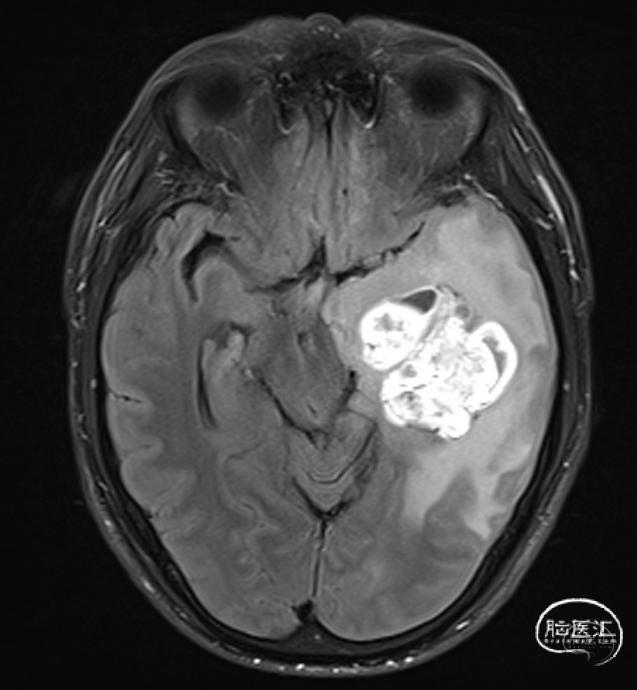

患者王**,52岁,女性。

患者以“头痛、头晕伴行走不稳半年,加重2天”入院。

入院查体:体温36.5℃;脉搏77次/分;血压140/76mmHg,神志清楚,精神差,查体合作,双侧瞳孔等大等圆,直径约2.5mm,对光反射敏捷,伸舌偏右,指鼻试验、轮替试验+,四肢肌力、肌张力正常,生理反射存在,病理征阴性,小脑征阳性。